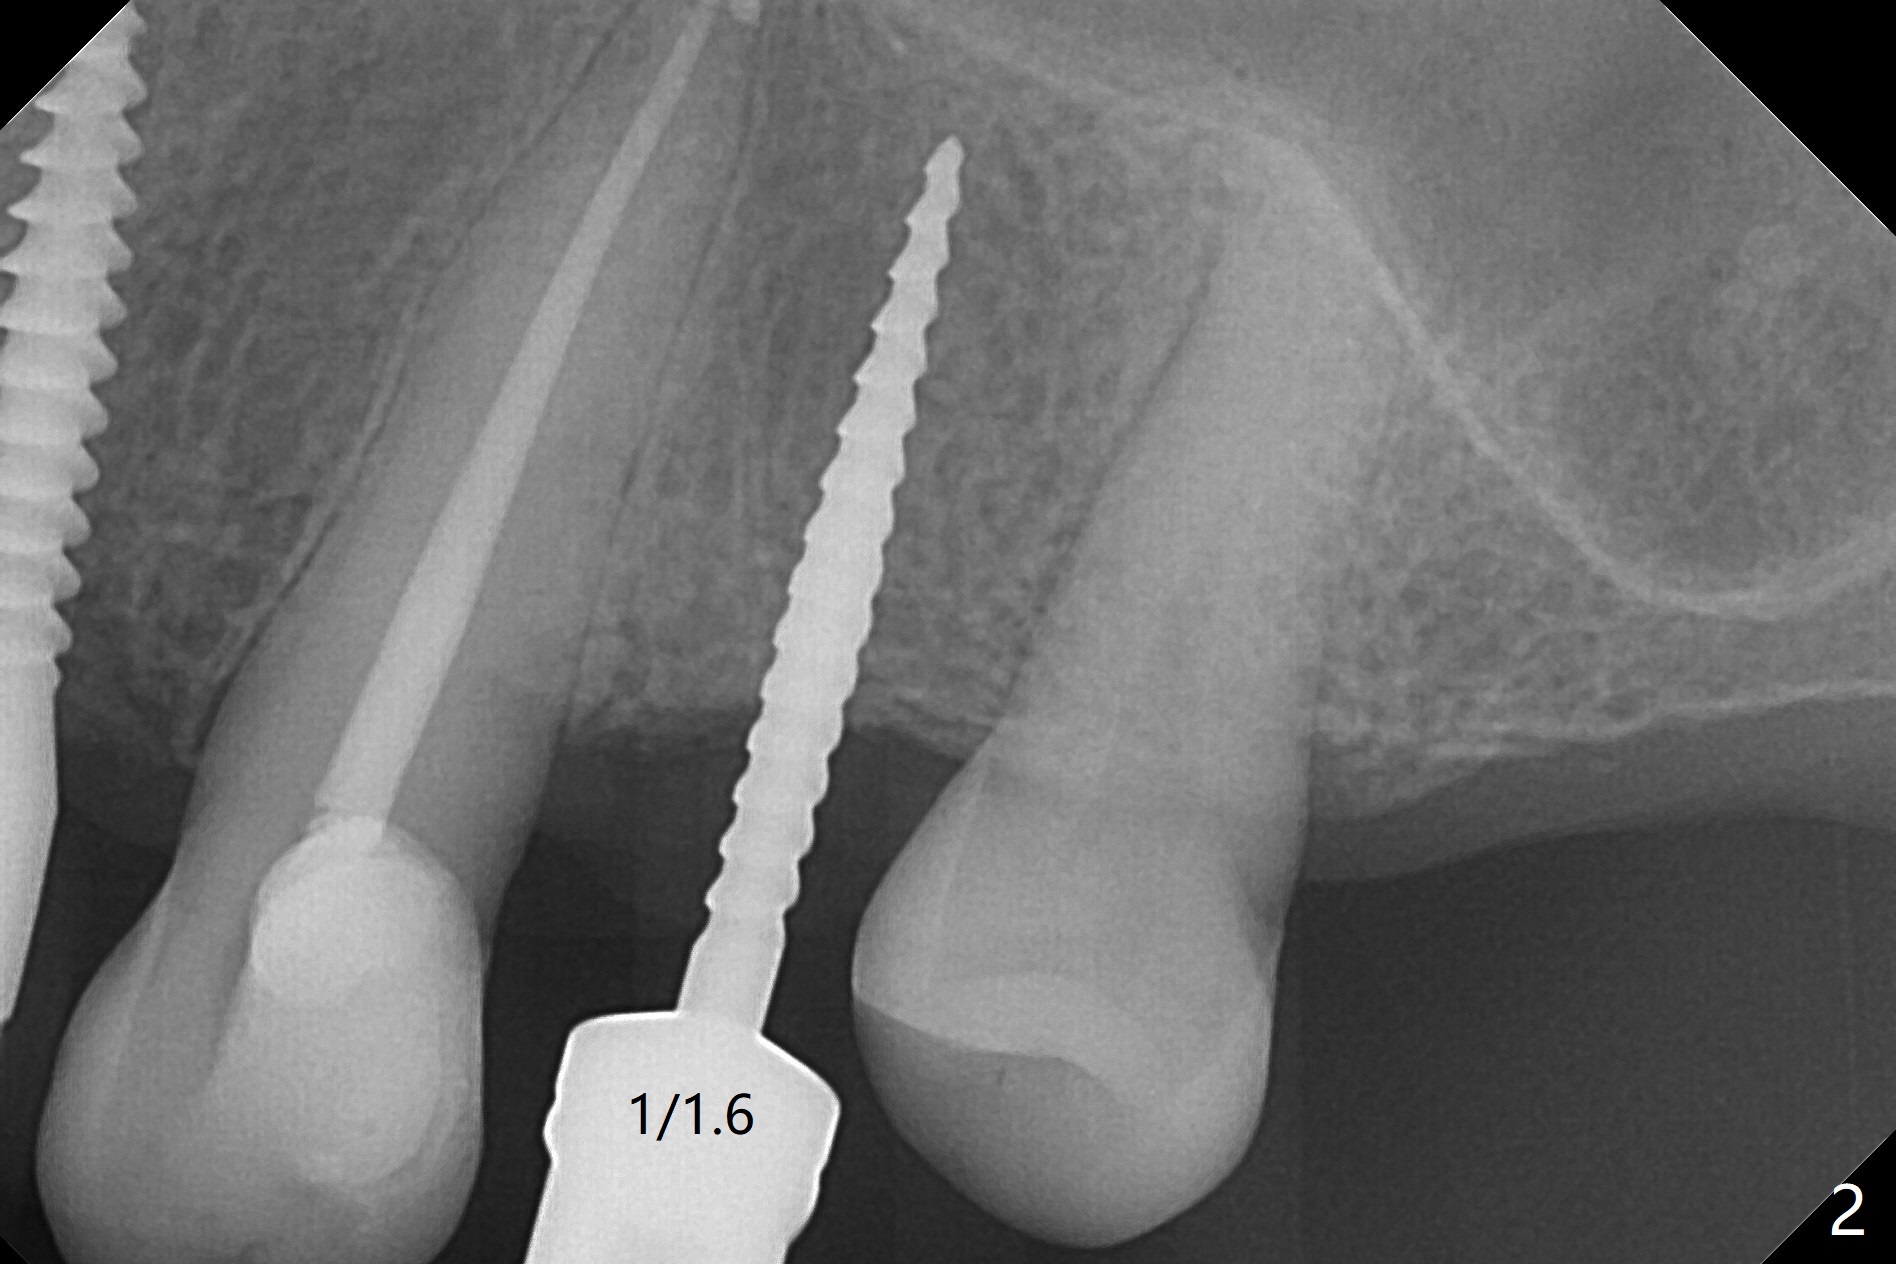

After removal of #10 sleeve and 3 spot adjustment, the guide is seated without satisfaction. When the guide is removed after pointed drill, the osteotomy seems distal (Fig.1). Incision is made with flap elevation for free hand osteotomy. A 1/1.6 mm bone expander is inserted after 1.2 mm drill, the trajectory appears to be right (Fig.2). As the osteotomy increases in diameter, the buccal plate feels to be vibratory. A 3.5x11.5 mm 1-piece implant placed initially is apparently away the sinus floor (Fig.3). Further placement (subcrestal, Fig.4) seems to be associated with more buccal plate perforation (Fig.6 *), which is repaired by bone graft. Since the implant at #10 appears to be doing okay 1.5 months postop (Fig.5), the implant at #12 is not removed immediately. A tunnel incision will be made for bone graft in the most apical concave areas (Fig.7). The osteotomy should have been made more palatal to reduce the chance of the buccal perforation. CBCT should have been taken while the 1/1.6 bone expander was in place.